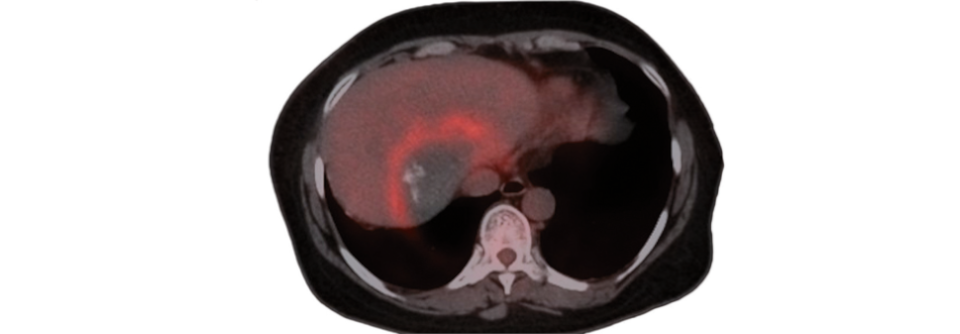

Fallen Ihnen bei Ihrem Zirrhosepatienten kognitive Einschränkungen oder Störungen der Motorik auf, sollten Sie an eine hepatische Enzephalopathie (HE) denken. Allerdings genügt die Beobachtung verdächtiger Symptome allein noch nicht für die Diagnose, betonen die Autoren der Leitlinie „Komplikationen der Leberzirrhose“. Zuvor müssen zahlreiche Differenzialdiagnosen ausgeschlossen werden, die sich ganz ähnlich präsentieren können.